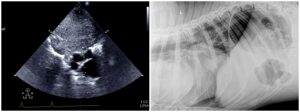

Esta es una sección realizada en colaboración de los compañeros veterinarios con los que trabaja DXIA, en la cual, compararemos imágenes reales, obtenidas durante la resolución quirúrgica, con imágenes ecográficas.

Una forma que puede ser interesante de colaboración y que nos ayuda a poder darle color a las imágenes obtenidas durante un estudio ecográfico seria comparar las imágenes reales que se obtienen durante las cirugías o intervenciones con las imágenes diagnósticas obtenidas durante el estudio ecográfico del paciente. Os quiero animar a todos a que mandéis dichas imágenes y a que este apartado crezca día a día.